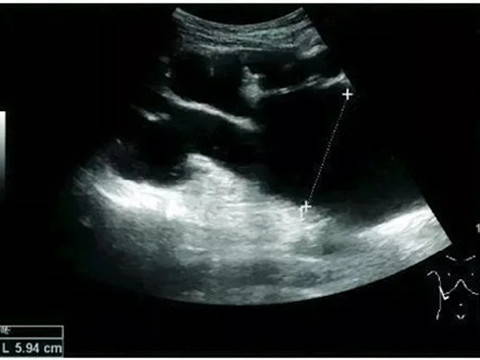

Renal Cyst

Most renal cysts are simple renal cysts that are round in shape and filled with fluid. The incidence of simple renal cysts in people over 50 years old is ≥50%. It is a benign lesion and no further evaluation is required.

Adult simple cyst, dashed distance: kidney length